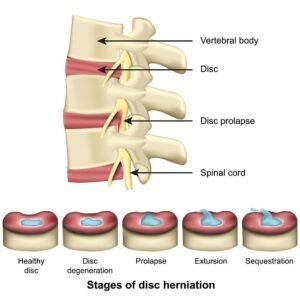

Междупрешленните дискове се намират между прешлените и действат като естествени амортисьори. Те помагат на гръбначния стълб да поема натоварването при движение, ходене, навеждане и вдигане на тежести. Всеки диск има външен фиброзен пръстен и по-меко вътрешно ядро. Когато структурата на диска отслабне или се увреди, част от него може да промени формата си и да започне да навлиза към гръбначния канал или към нервните коренчета.

Когато дискът е здрав, тези структури работят балансирано. При дегенерация, хронично натоварване, травма или повтарящи се микротравми външният пръстен може да отслабне, а вътрешното ядро да започне да променя позицията си.

Дисковата херния обикновено не се появява изведнъж в напълно здрав диск. В много случаи тя се развива постепенно. Често първо настъпват дегенеративни промени, намаляване на водното съдържание на диска и отслабване на неговата структура. С времето дискът губи част от своята еластичност и способност да поема натоварването.

При определени движения, продължително механично натоварване, неправилна стойка, повтарящо се навеждане или вдигане на тежести дискът може да започне да се деформира. В някои случаи това води само до промяна във формата му, а в други може да се стигне до по-изразено изместване на дисков материал и дразнене на нервните структури.

Етапи на дисковата херния

1. Дегенерация на диска

Това е началният етап, при който дискът започва да губи своята хидратация и еластичност. Височината му може леко да намалее, а структурата му да стане по-малко устойчива на натоварване. На този етап все още не винаги има изразена херния, но дискът вече е по-уязвим.

2. Булджинг диск

При булджинг диск междупрешленният диск се разширява дифузно извън нормалните си граници. Това означава, че дискът е изпъкнал, но без ясно ограничено излизане на една част от него. Булджингът не винаги причинява симптоми, но когато е съпроводен с възпаление или натиск върху близки структури, може да доведе до болка и скованост.

3. Дискова протрузия

Това е следващ етап, при който вътрешната част на диска започва да избутва външния фиброзен пръстен на определено място. Външният слой все още не е напълно разкъсан, но вече има по-ясно изразено локално издуване. Именно на този етап често се появяват по-силни симптоми, особено ако има контакт с нервно коренче.

4. Дискова екструзия

При екструзията част от дисковия материал преминава през увредения външен слой и излиза по-ясно извън нормалните граници на диска. Това е по-напреднал стадий, при който вероятността от притискане или силно дразнене на нервните структури е по-висока.

5. Секвестрация

Това е най-напредналият етап. Част от дисковия материал се отделя от основния диск и може да остане свободно разположена в гръбначния канал. При този стадий симптомите могат да бъдат по-изразени и често се наблюдава по-силно нервно дразнене.

Важно е да се подчертае, че MRI находката и симптомите невинаги съвпадат напълно. Понякога човек може да има изразени образни промени и сравнително умерени оплаквания, а в други случаи дори по-малка херния може да причини силна болка в зависимост от това къде точно се намира и кои структури засяга.